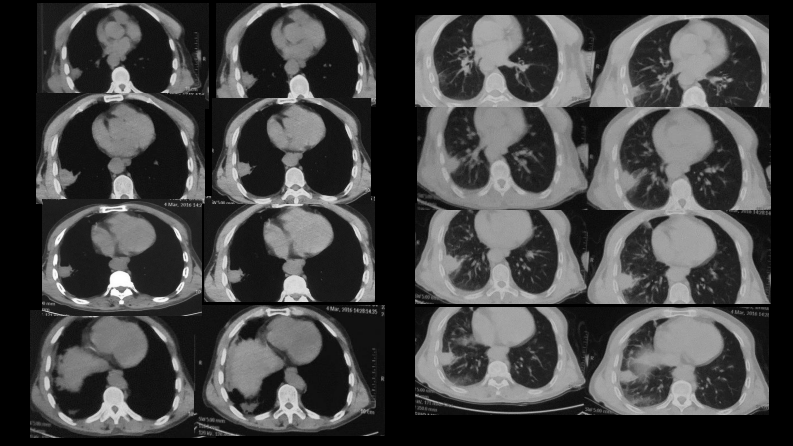

肺部肿块有效的影像检查选择.pdf